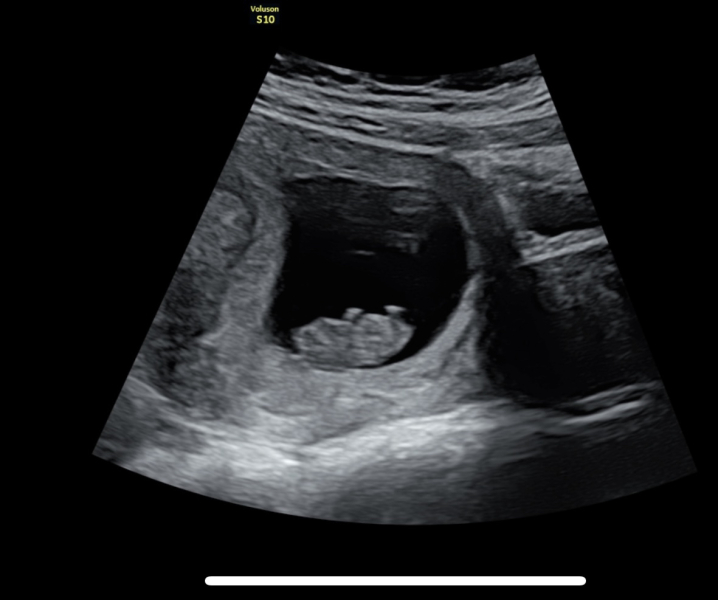

Scotti84 · 23/12/2022 09:05

Just had my scan, measuring at around 11 weeks, due date around 14th July. Baby was jumping around and wiggling its bum. Booked in for a harmony test on 3rd Jan where we will also test to find the gender cos we're impatient and also have absolutely no idea of a name of its a girl.